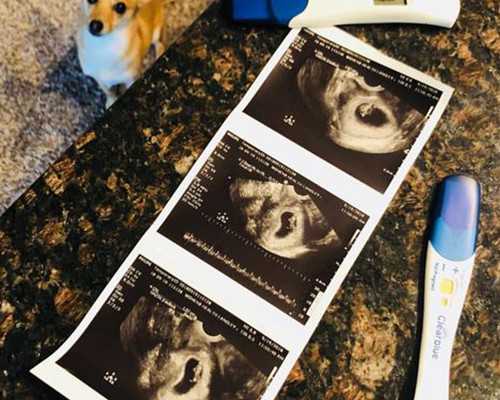

早孕試紙一條杠,是不是沒懷孕?

- 驗(yàn)孕試紙什么時候能測出懷孕?

- 驗(yàn)孕棒和抽血,哪個結(jié)果更準(zhǔn)?

- 驗(yàn)孕試紙準(zhǔn)不準(zhǔn)?什么時候用最合適

- 驗(yàn)孕試紙一個月后測準(zhǔn)不準(zhǔn)

- 驗(yàn)孕棒怎么用才準(zhǔn)?手把手教你正確操作

- 早早孕試紙?jiān)趺从茫窟@些細(xì)節(jié)你得知道

- 早孕試紙?jiān)趺从煤涂唇Y(jié)果?簡單幾步教會你

- 早孕試紙去哪買更放心?

- 早孕試紙的正確用法,這些細(xì)節(jié)你可能不知道